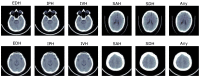

Intracranial hemorrhage (ICH) can lead to death or disability, which requires immediate action from radiologists. Due to the heavy workload, less experienced staff, and the complexity of subtle hemorrhages, a more intelligent and automated system is necessary to detect ICH. In literature, many artificial-intelligence-based methods are proposed. However, they are less accurate for ICH detection and subtype classification. Therefore, in this paper, we present a new methodology to improve the detection and subtype classification of ICH based on two parallel paths and a boosting technique. The first path employs the architecture of ResNet101-V2 to extract potential features from windowed slices, whereas Inception-V4 captures significant spatial information in the second path. Afterwards, the detection and subtype classification of ICH is performed by the light gradient boosting machine (LGBM) using the outputs of ResNet101-V2 and Inception-V4. Thus, the combined solution, known as ResNet101-V2, Inception-V4, and LGBM (Res-Inc-LGBM), is trained and tested over the brain computed tomography (CT) scans of CQ500 and Radiological Society of North America (RSNA) datasets. The experimental results state that the proposed solution efficiently obtains 97.7% accuracy, 96.5% sensitivity, and 97.4% F1 score using the RSNA dataset. Moreover, the proposed Res-Inc-LGBM outperforms the standard benchmarks for the detection and subtype classification of ICH regarding the accuracy, sensitivity, and F1 score. The results prove the significance of the proposed solution for its real-time application.